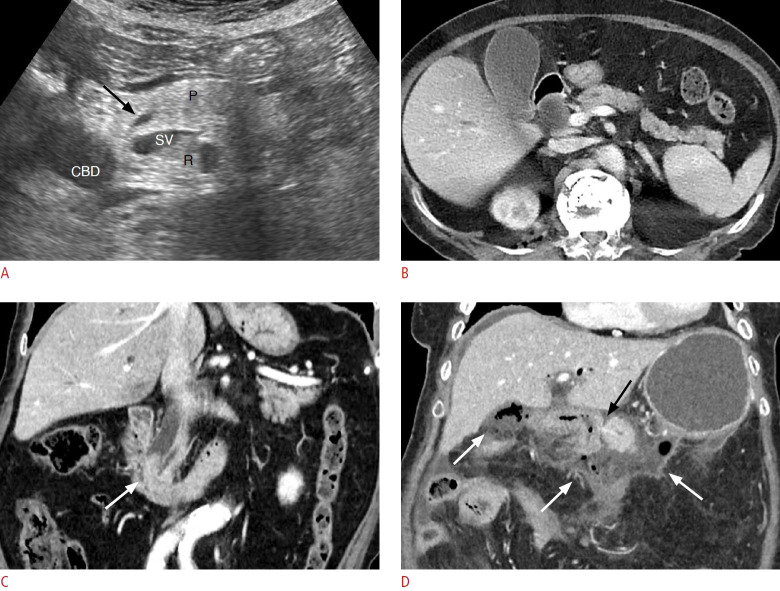

Methods: A retrospective study was conducted with 94 patients who underwent pancreatectomy between April 2006 and March 2021. The severity of HP on US was classified into two categories (normal to mild vs. moderate to severe [obvious HP]). Multiple preoperative and intraoperative parameters were analyzed to predict CR-POPF.

Results: Out of the 94 patients, CR-POPF occurred in 21 (22%) patients, and obvious HP was observed in 30 (32%). Univariate analysis revealed that moderate to severe HP (obvious HP) was significantly associated with an increased incidence of CR-POPF (P<0.001). Factors such as the absence of pancreatitis, a small main pancreatic duct (<3 mm), intraoperative soft pancreas, increased body mass index, and lower pancreatic attenuation and attenuation index were also associated with CR-POPF (all P<0.05). Multivariate analysis showed that obvious HP and soft pancreatic texture were independent predictors of CR-POPF, with odds ratios of 11.53 (P=0.001) and 14.12 (P=0.003), respectively. The combination of obvious HP and soft pancreatic texture provided the most accurate prediction for CR-POPF.

Conclusion: The severity of HP, as observed on preoperative US, was significantly associated with CR-POPF. Severe HP may serve as a clinically useful predictor of POPF, especially when evaluated alongside the intraoperative pancreatic texture.